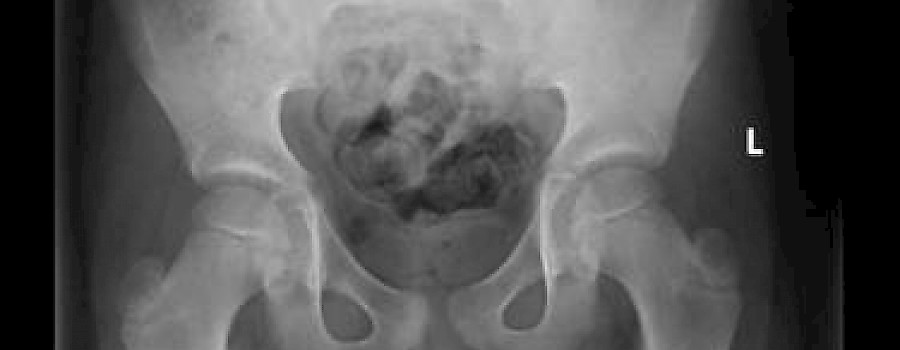

Ein 57-jähriger Patient in mittelschwer reduziertem AZ und magerem EZ, wach, klar orientiert und adäquat, blaße Hautfarbe stellt sich in der Notaufnahme vor und wurde zur Abklärung einer abnormen Gewichtsabnahme stationär aufgenommen.

Es gibt schon manchmal komische Situationen in einer Röntgenabteilung. So wie in diesem Falle...,

Ganz normales aus einer Notfallambulanz